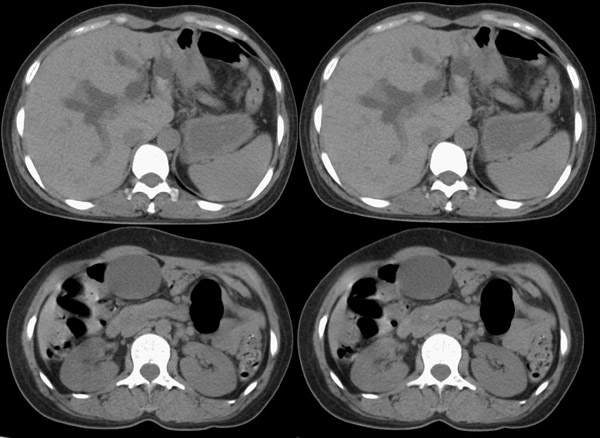

整个胆道系统内可见多发蛔虫钙化改变,胆道扩张.

胆总管结石并肝内外胆管扩张、肝左叶肝内胆管结石、胆囊大。

行胆囊切除术及胆总管探查术:探查见肝脏大小正常,肝缘稍钝,肝表面光整,胆囊大小12*3*3cm3,壁水肿增厚约0。5cm,张力稍高,胆囊与大网膜呈纤维粘连;胆总管宽约2cm,壁明显增厚,触摸胆总管,隐约可触及一条状物,于胆总管做一长约1、5cm的纵行切口,用取石钳在胆总管内取出一条长约16cm长黑色的长条状物,较脆易折断,宽约0、6cm,证实为蛔虫尸体。用探子往下探,未发现下端结石最后诊断:胆道蛔虫症继发胆系梗阻性扩张。

疑惑:1、ct表现胆总管下端有结石影,但手术中未发现???

2、胆总管下端若是阳性结石,那么这条16*0、6cm2的大蛔虫是如何进入胆总管的?!

结合胆道蛔虫病史,蛔虫性胆系结石并胆系梗阻能明确诊断。至于说没有发现胆总管下端阳性结石,因为已经取出来了。